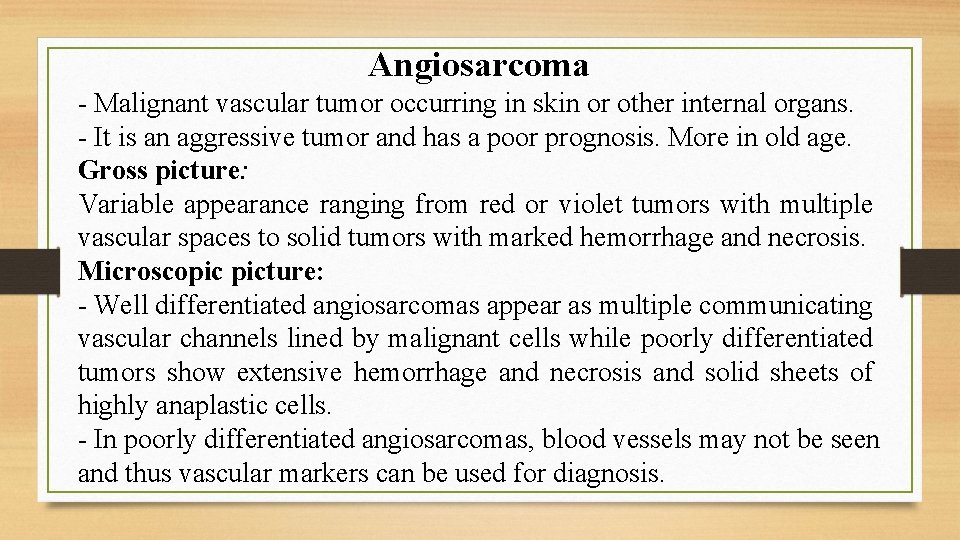

Angiosarcoma - Malignant vascular tumor occurring in skin or other internal organs. - It is an aggressive tumor and has a poor prognosis. More in old age. Gross picture: Variable appearance ranging from red or violet tumors with multiple vascular spaces to solid tumors with marked hemorrhage and necrosis. Microscopic picture: - Well differentiated angiosarcomas appear as multiple communicating vascular channels lined by malignant cells while poorly differentiated tumors show extensive hemorrhage and necrosis and solid sheets of highly anaplastic cells. - In poorly differentiated angiosarcomas, blood vessels may not be seen and thus vascular markers can be used for diagnosis.